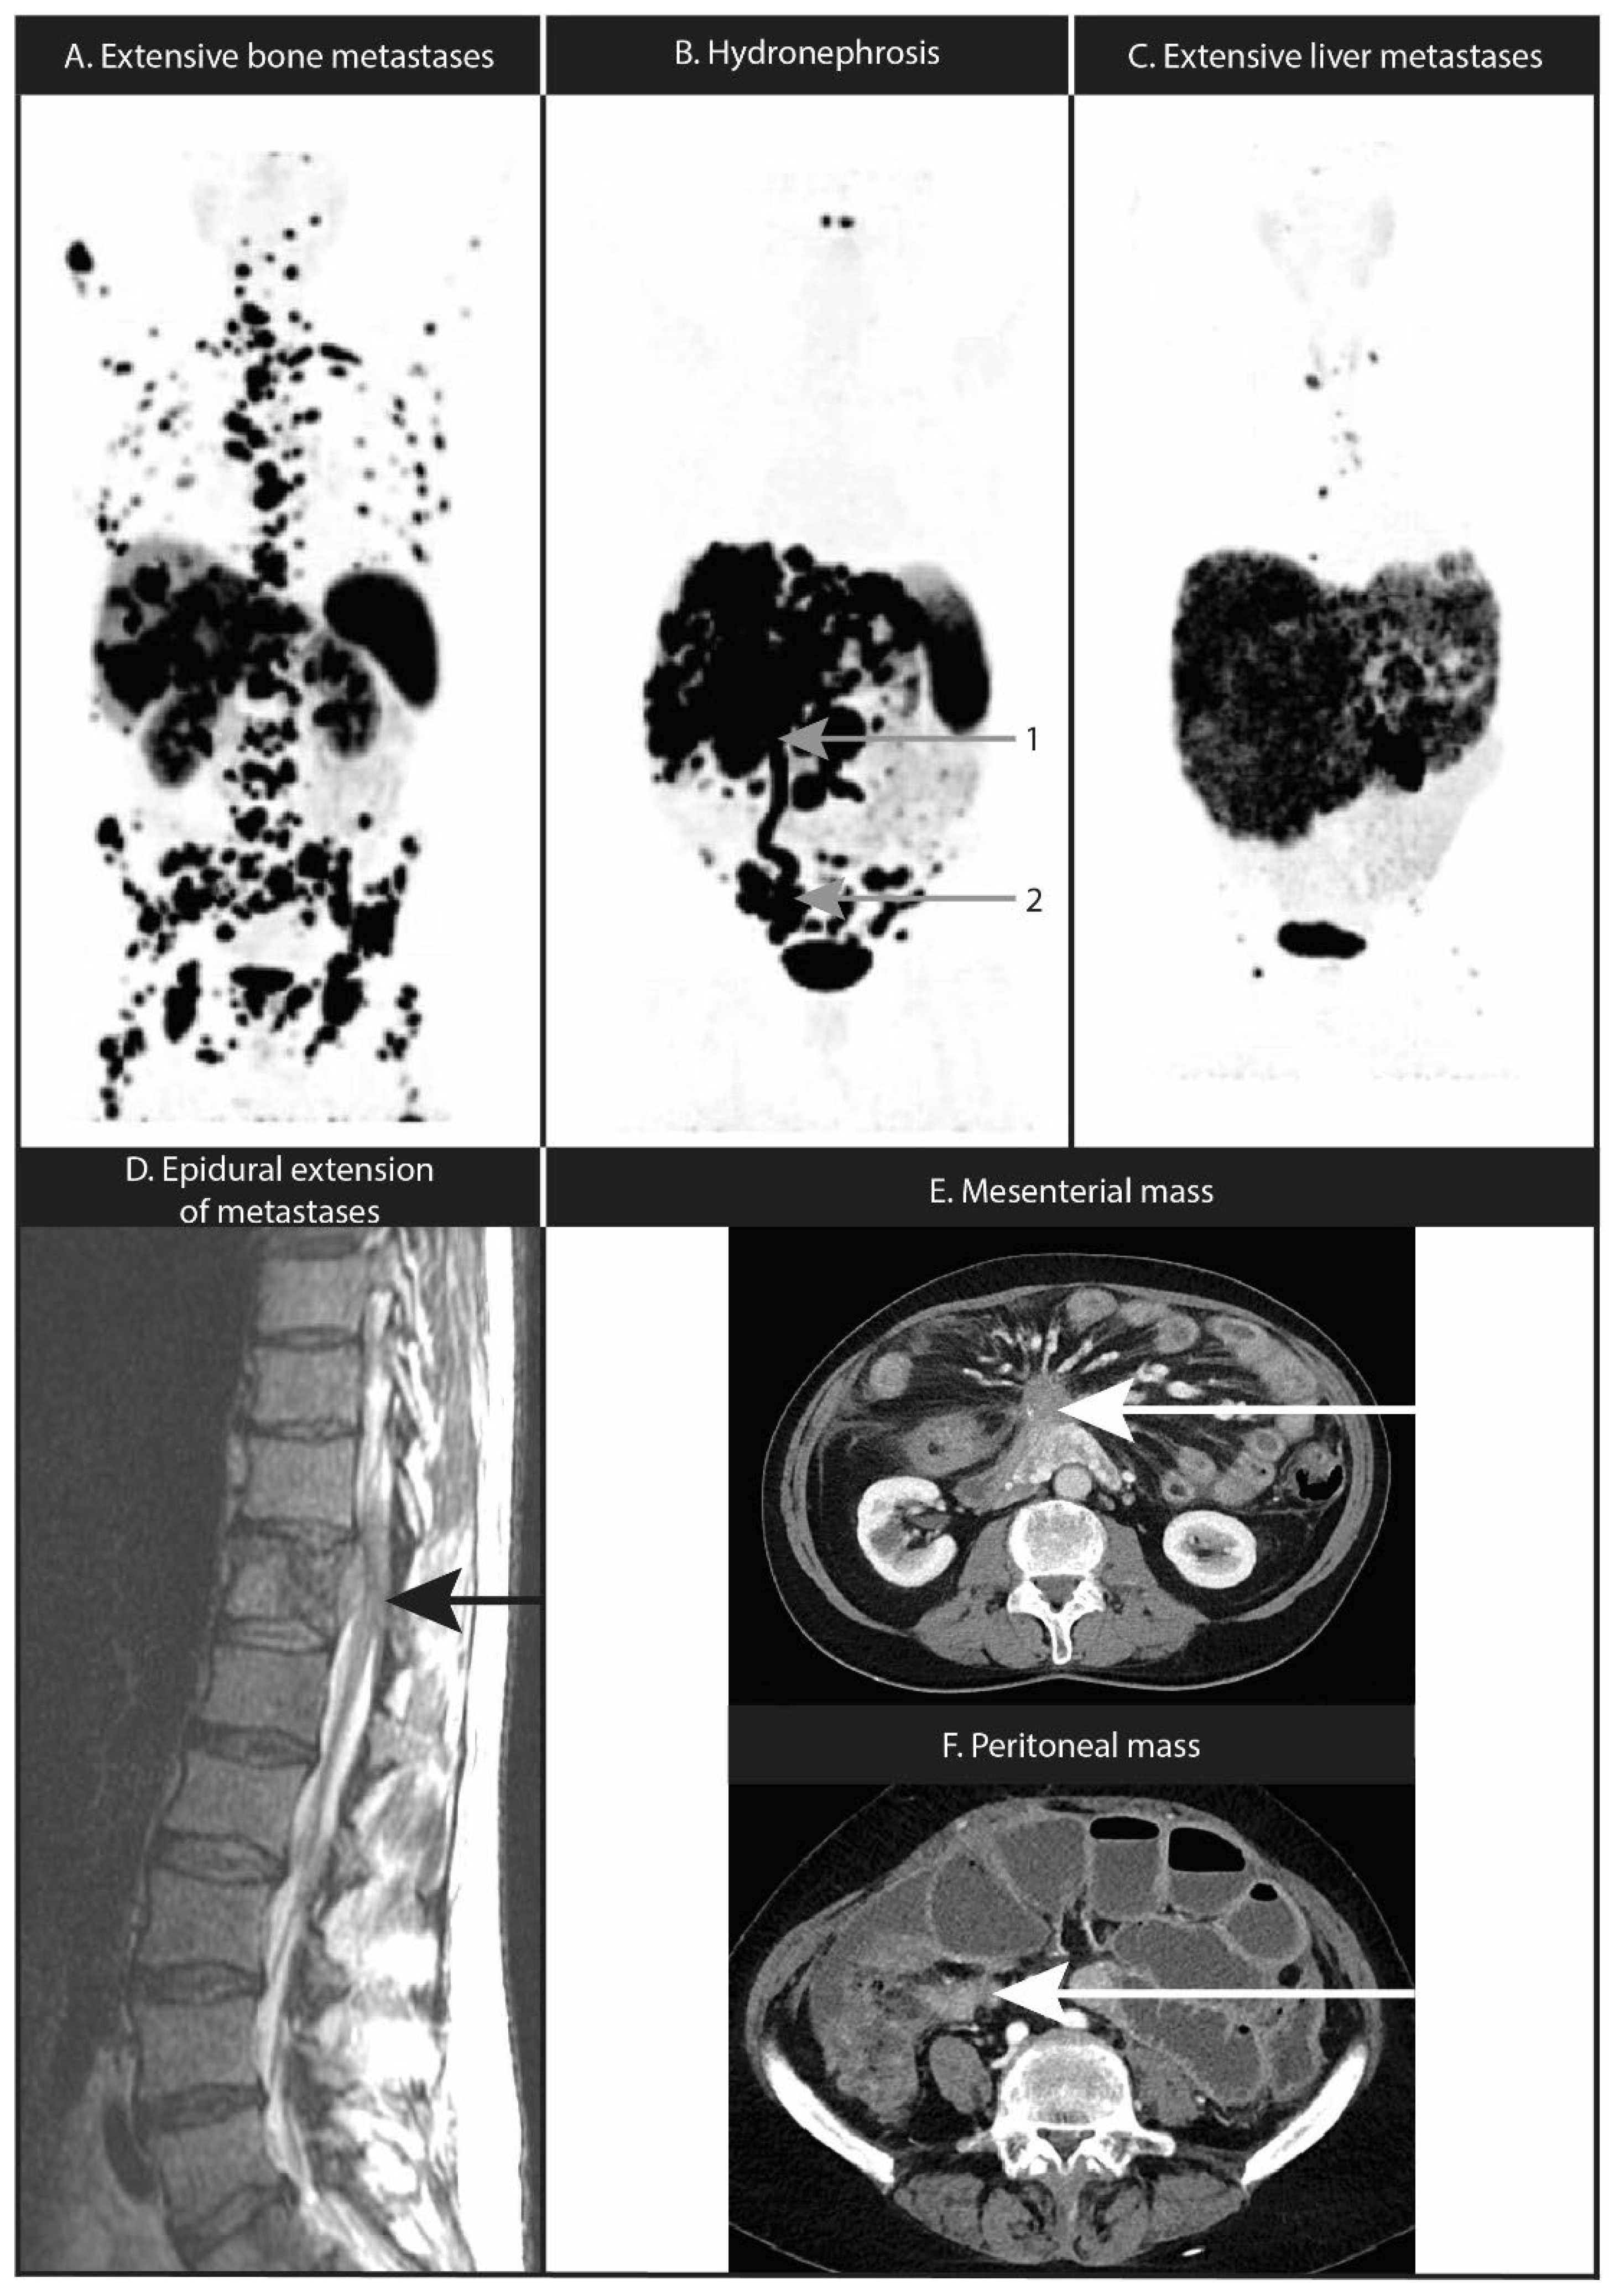

10. Nervous System Location or Compression

11. Mesenteric Fibrosis and Mesenteric or Peritoneal Metastases

3.3. Prediction of Response to PRRT